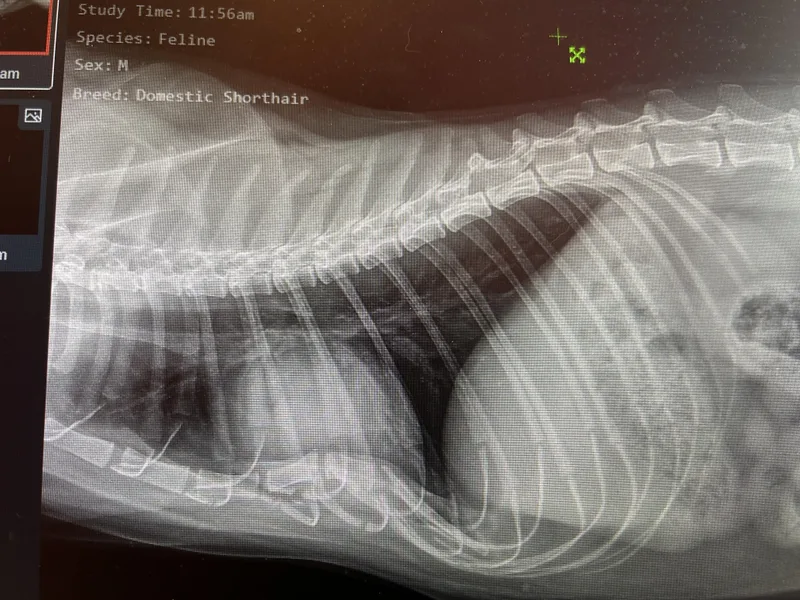

Meet Our Jetson 🖤 Intake: 1/19/26 Estimated DOB: July 2021 Jetson had been a stray on the southeast side for about two years before finally getting his chance to come inside. When he arrived, he was dealing with significant skin issues that likely began as flea allergy dermatitis. His skin was scaly and scabby—almost like a lizard—but thankfully much softer! 😊 With topical fatty acid supplementation and good care, his coat is already improving and getting back into tip-top shape. For now, he can’t wear a collar, as his fur will fall out where it rubs, but that should improve as his skin continues to heal. Despite everything he had been through, Jetson was SUPER friendly with both his rescuer and all of us at Feline Wellness Center. He also came in with a mild, low-grade anemia, which we are monitoring. Jetson also has an interesting and very rare skeletal condition called pectus excavatum—Latin for “hollow breast.” This condition describes a chest wall deformity where the rib cartilage and sternum (chest bone) do not form correctly during fetal development. It’s sometimes referred to as funnel chest or flat-chested syndrome in kittens. In Jetson’s case, however, he was incredibly lucky. His condition is mild, you can’t tell just by looking at him, and it’s not easily felt during an exam. There is only minimal displacement of the organs in his chest and no respiratory or cardiac complications, meaning it does not affect his quality of life. Jetson is becoming more comfortable with his new surroundings every day. He tends to keep to himself and quietly observe the world around him, but he has never shown any aggression and is a very sweet boy. He can be a little timid at times, so he would likely do best in a calmer, less active home. Older kids who could spend time with him and help him learn that it’s okay to relax, play, and enjoy life might be a wonderful fit. Jetson could do well with a feline friend or two; a home with dogs may not be his ideal match, but one mellow pooch could be considered. Jetson is gentle, handsome, and loves being brushed. Soon his coat will be sleek and shiny again! He’s a pretty laid-back guy who enjoys hanging out up high and absolutely LOVES window watching. Bird TV is one of his favorite programs. All in all, Jetson is a sweet-natured, easygoing boy and an all-around great guy who’s ready for the next chapter of his life.